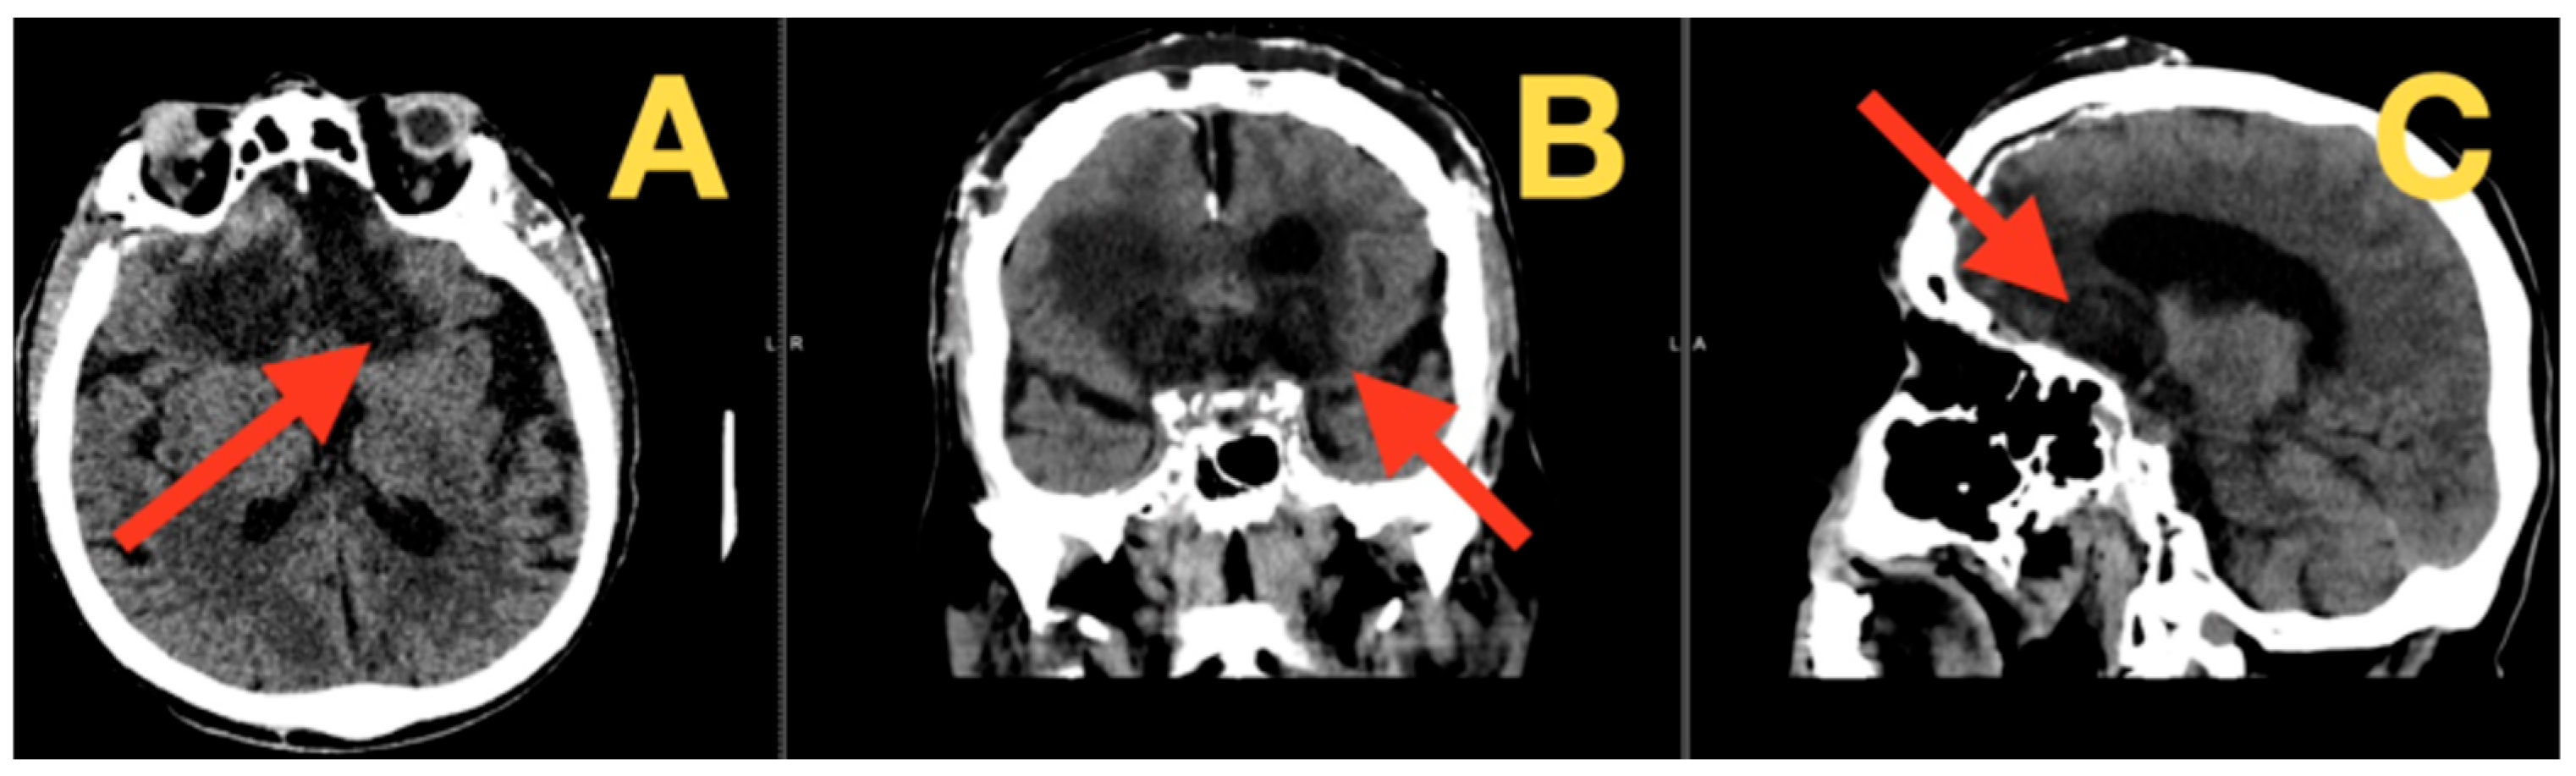

2.4. Preoperative Imaging and Quantitative Metrics